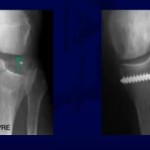

Radiographic Landmarks and Schöttle’s Point

Schöttle’s point is widely described for femoral tunnel placement.

Radiographic landmarks are not perfectly reproducible.

Fluoroscopy alone may not guarantee accuracy.

Studies show variability in tunnel placement even among expert surgeons.

Radiographic landmarks should guide but not dictate tunnel placement.